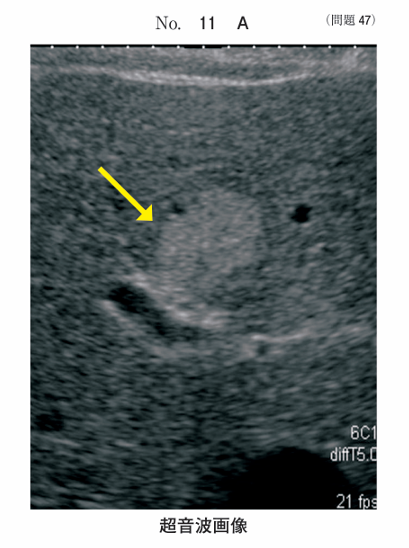

午前/問題47

同一腫瘍の超音波画像別冊No. 11AとMR像別冊No. 11Bを別に示す。矢印の腫瘤の主成分はどれか。

1.水

2.血液

3.脂肪

4.線維

5.カルシウム